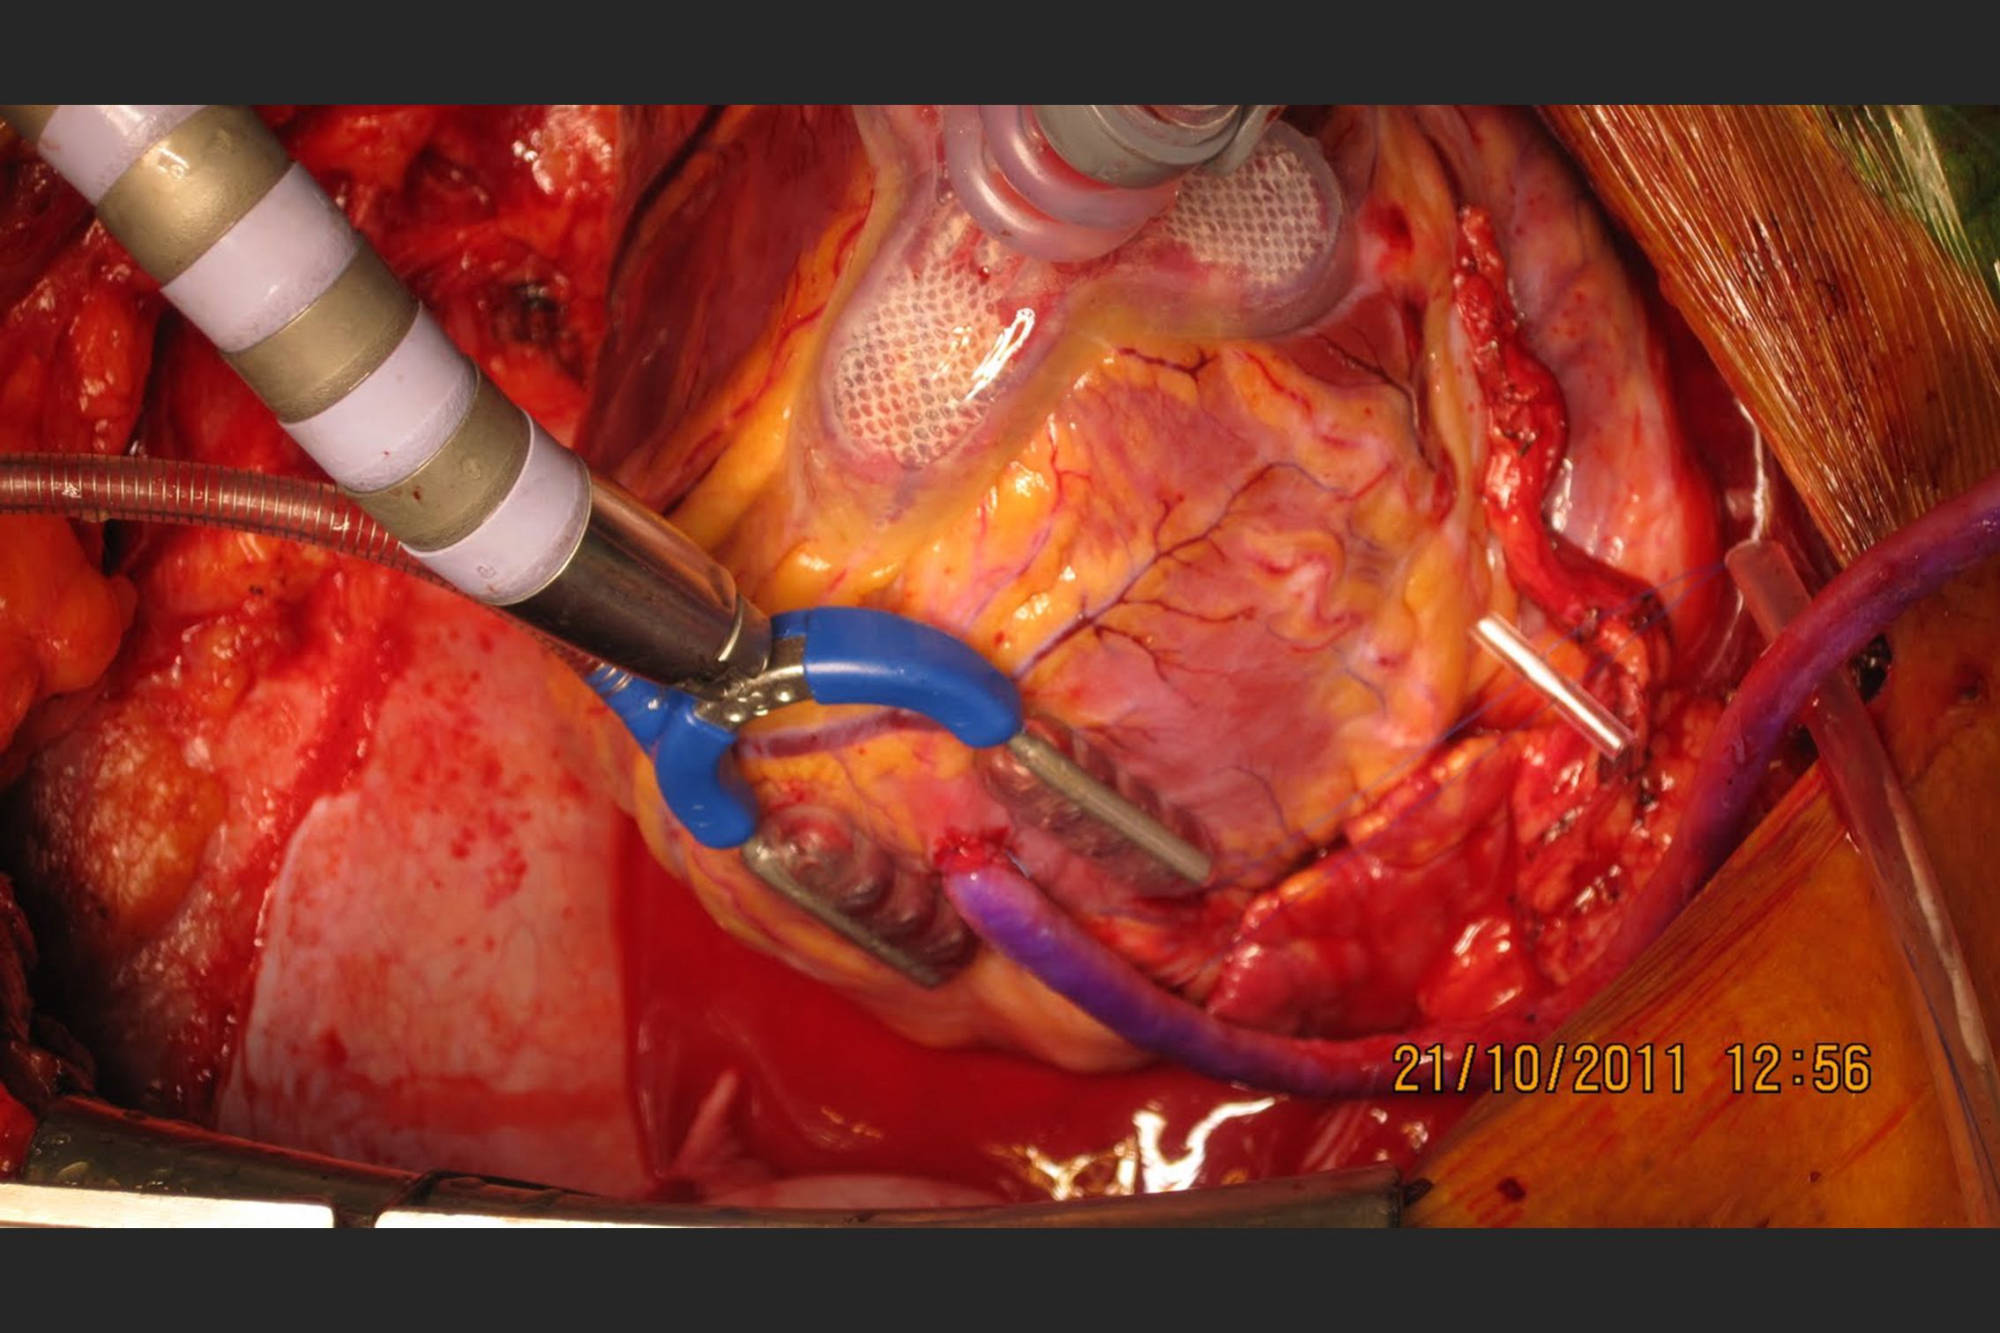

Heart Transplantation

Led Malabar's first successful heart transplantation done at Metromed International Cardiac Centre on a 54 year old patient with end stage heart disease. Donor heart was harvested from a 28 year old gunshot victim in Kannur and brought to MICC through a green corridor. The transplanted patient is healthy and on minimal medication. For end stage cardiac disease, heart transplantation is the gold standard. Post transplant, they have a near normal life.